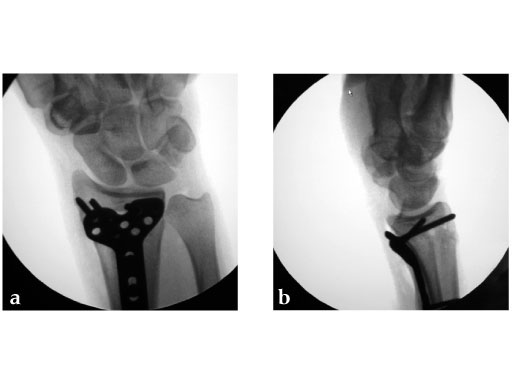

28-year-old woman.

Fig 1ab: X-rays preoperative.